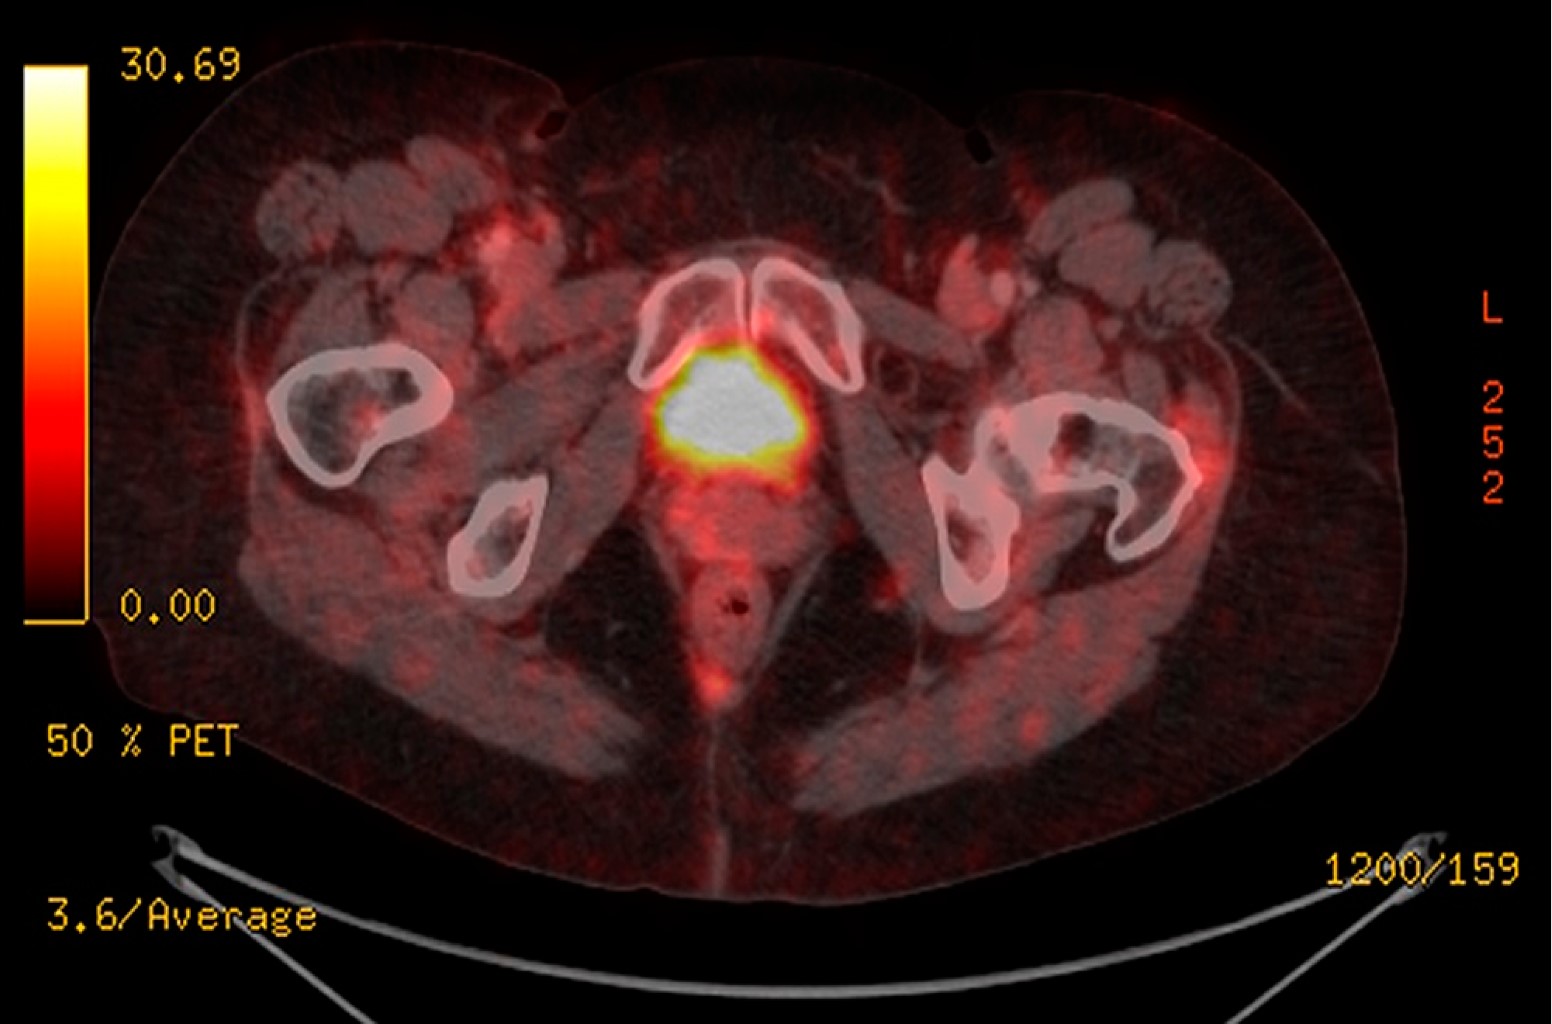

Mujer de 70 años de edad sin antecedentes médicos de importancia. Un mes previo al diagnóstico detectó una tumoración en la ingle derecha de crecimiento progresivo y acelerado. Acudió con un médico, quien ante los hallazgos sospechó de un tumor maligno y solicitó PET CT, el cual mostró una imagen sugerente de masa de tejidos blandos en la región inguinal derecha de 45 mm en su eje corto que refuerza con la aplicación de medio de contraste, alternando con imágenes hipodensas en su interior, con adecuada interfase con los músculos adyacentes, la cual tiene SUV máximo de 9.8 y en la adquisición tardía SUV máximo de 10.6. Fue sometida a resección de la lesión y el estudio histopatológico reveló linfangioleimiomatosis con tumor neuroectodérmico primitivo (sarcoma de Ewing), CD99 positivo, con bajo índice de proliferación. Márgenes quirúrgicos negativos. Se realizó una segunda revisión por parte de patología y se corroboró lo anterior, ganglio linfático infiltrado por tumor neuroectodérmico primitivo/sarcoma de Ewing. Después fue enviada para valorar RT postoperatoria. De acuerdo con la información existente se consideró candidata al tratamiento, por lo que brindamos RT conformada al sitio original del tumor (previa fusión con PET CT prequirúrgico) con márgenes para CTV de 1.5 cm y para PTV de 0.5 cm. La dosis prescrita fue de 50.4 Gy en 28 fracciones (1.8 Gy/fracción) (Figura 1). Durante la administración de la radioterapia no hubo toxicidad relacionada con el tratamiento. Actualmente la paciente tiene una supervivencia libre de enfermedad de 45 meses y no hay toxicidad debido al tratamiento. En el último PET CT de control no hay datos de recurrencia de la enfermedad (Figura 2).

Figura 1